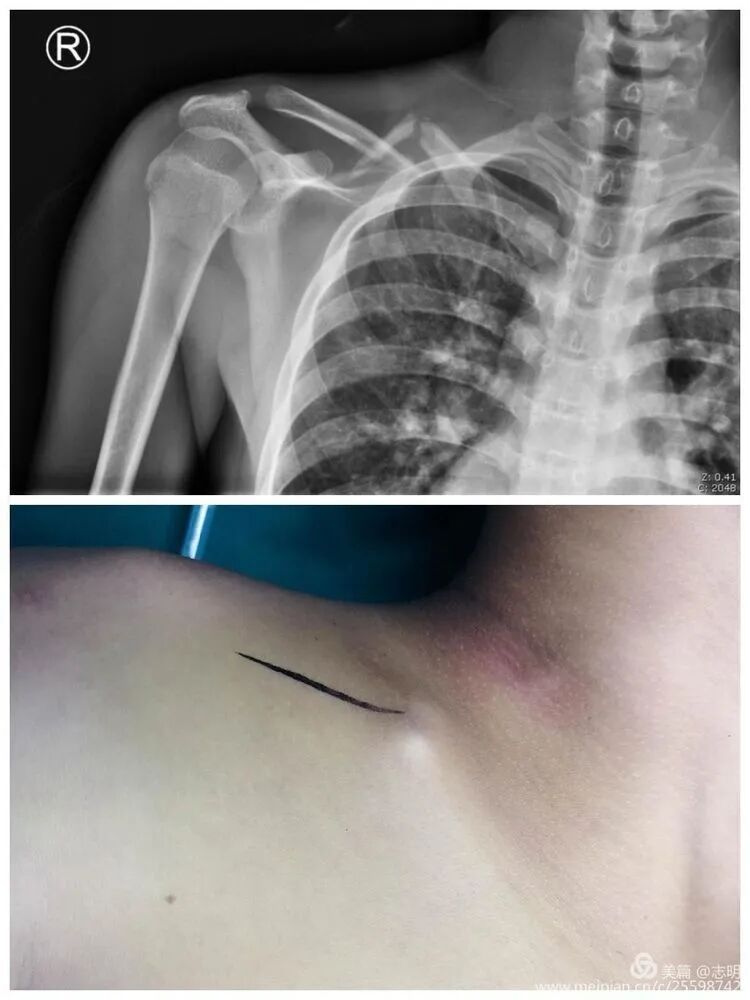

Imaging Review:

- Standard Radiographs: Anteroposterior (AP) view of the shoulder with 10-15 degrees of cephalic tilt, and a true AP clavicle view (0 degrees tilt) are essential. These provide initial assessment of fracture pattern, displacement, and shortening.

- Computed Tomography (CT) Scan: Highly recommended, especially for comminuted fractures, articular involvement (medial or lateral), or suspicion of neurovascular injury. A 3D reconstruction helps visualize fracture fragments, assess shortening and rotation, and plan plate trajectory.

- Standard Radiographs: Acquire high-quality anteroposterior (AP) views of the shoulder with a 10-15 degree cephalic tilt, along with a true AP clavicle view (0 degrees tilt). These projections are crucial for initial assessment of the fracture pattern, the degree and direction of displacement, and any significant shortening.

-

Computed Tomography (CT) Scan:

A CT scan, especially with 3D reconstructions, is highly recommended for comminuted fractures, fractures with suspected articular involvement (medial or lateral ends), or when neurovascular injury is a concern. The 3D reconstruction provides invaluable insights into fragment orientation, axial rotation, and the true extent of shortening, allowing for precise pre-operative templating of plate trajectory and screw placement.

(Example of pre-operative imaging, likely an X-ray showing fracture).